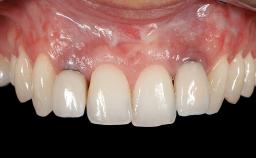

Soft-Tissue Volume Augmentation Using a Connective-Tissue Graft Harvested from the Maxillary Tuberosity

In 1983, a 51-year-old non-smoking patient was referred for the treatment of moderate chronic periodontitis. At the initial examination, 47% of sites exhibited probing depths of 4 to 6 mm. Periodontal therapy consisted of initial periodontal treatment including oral-hygiene instructions and supra- and subgingival debridement, followed by periodontal surgery to eliminate residual pockets.